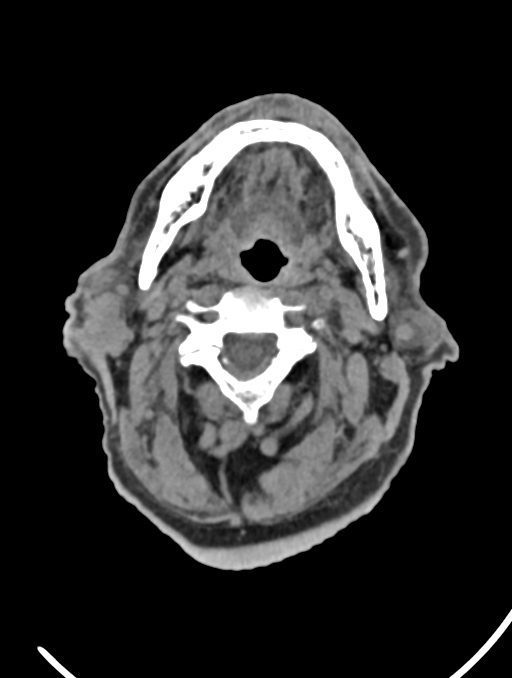

در سی تی اسکن ادنوم پاروتید، دستگاه تصاویری عرضی مقطع ایی از گوش در ناحیه سر و صروت ایجاد می کند. این تصویربرداری از اشعه ایکس برای ایجاد تصویر استفاده می کند.

در سي تي اسکن اسپيرال نازو فارنکس با و بدون کنتراست (مولتي ديدکتور 16 با مقاطع ظريف و بازسازي هاي ساژيتال و کرونال):

– توده نسج نرمي به ابعاد mm 40 x 45 x 60 در ناحيه پاروتيد راست، با enhancement هتروژن پس از تزريق کنتراست مشهود است که مطرح کننده آدنوم پاروتيد مي باشد.

– شواهدي از تهاجم توده به استخوان و عروق اطراف مشهود نيست .

– کلسيفيکاسيون در ديواره شريان هاي کاروتيد دو طرف مشهود است .